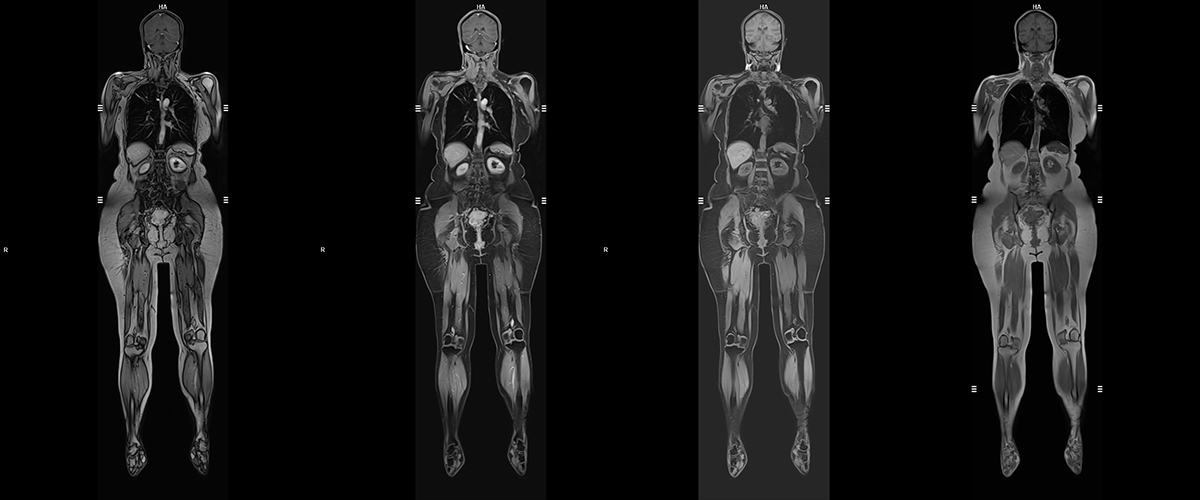

Tüm vücut MR, vücuttaki tüm organların ve dokuların bir seferde incelenmesine olanak tanıyan, non-invaziv bir görüntüleme yöntemidir. Bu yöntem, özellikle erken teşhis ve hastalıkların yayılımını değerlendirmek için kullanılır. Radyasyon içermemesi ve ayrıntılı görüntüler sunması nedeniyle yaygın olarak tercih edilir.

Kapsamlı Görüntüleme: Beyin, omurga, akciğerler, karaciğer, böbrekler, kaslar, kemikler ve damarlar dahil olmak üzere tüm vücut bölümlerini tarar.

Manyetik Alan Kullanımı: Görüntüleme manyetik alanlar ve radyo dalgaları ile yapılır, radyasyon içermez.

• Yüksek Görüntü Kalitesi: Tüm organ ve dokuların ayrıntılı incelenmesini sağlar.